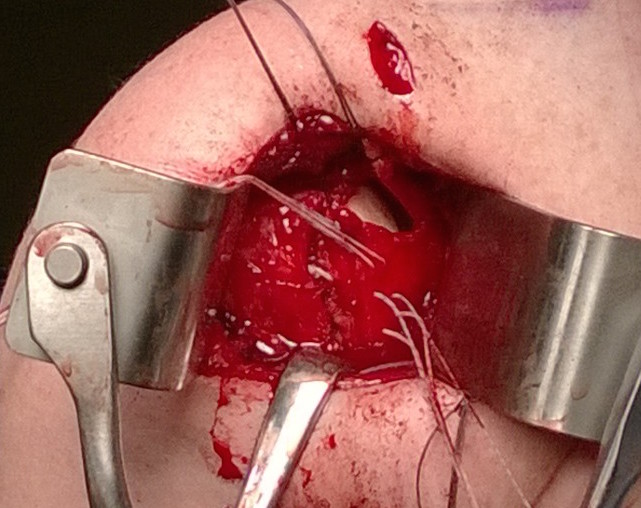

Open posterior capsular plication +/- allograft reconstruction +/- subscapularis shift / Putti-Platt

Technique

AO surgical foundation posterior approach glenoid / scapula

Arthroscopic posterior capsule reconstruction with acellular dermal allograft PDF

Open posterior capsular reconstruction with acellular dermal allograft PDF / video

Lateral Position

- vertical incision over glenohumeral joint

- elevate deltoid or split deltoid

- interval: between supraspinatus and infraspinatus

- interval: between infraspinaus and teres minor

- can detach infraspinatus tendon and elevate off capsule

- suprascapular nerve 1.5cm medial to glenoid

- axillary nerve below teres minor

- perform capsular plication / capsular shift

- +/- lateral advancement of infraspinatus

Open posterior approach in beach chair with detachment of deltoid

Infraspinatus tenotomy

Open posterior capsular plication in lateral position